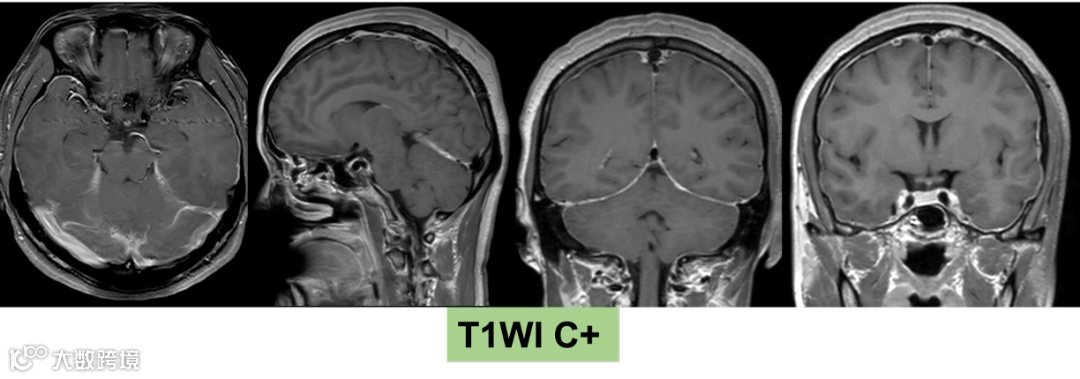

2025-07-14 颅脑MR平扫+增强+颈胸腰椎MR平扫

影像号:3462706

影像学表现